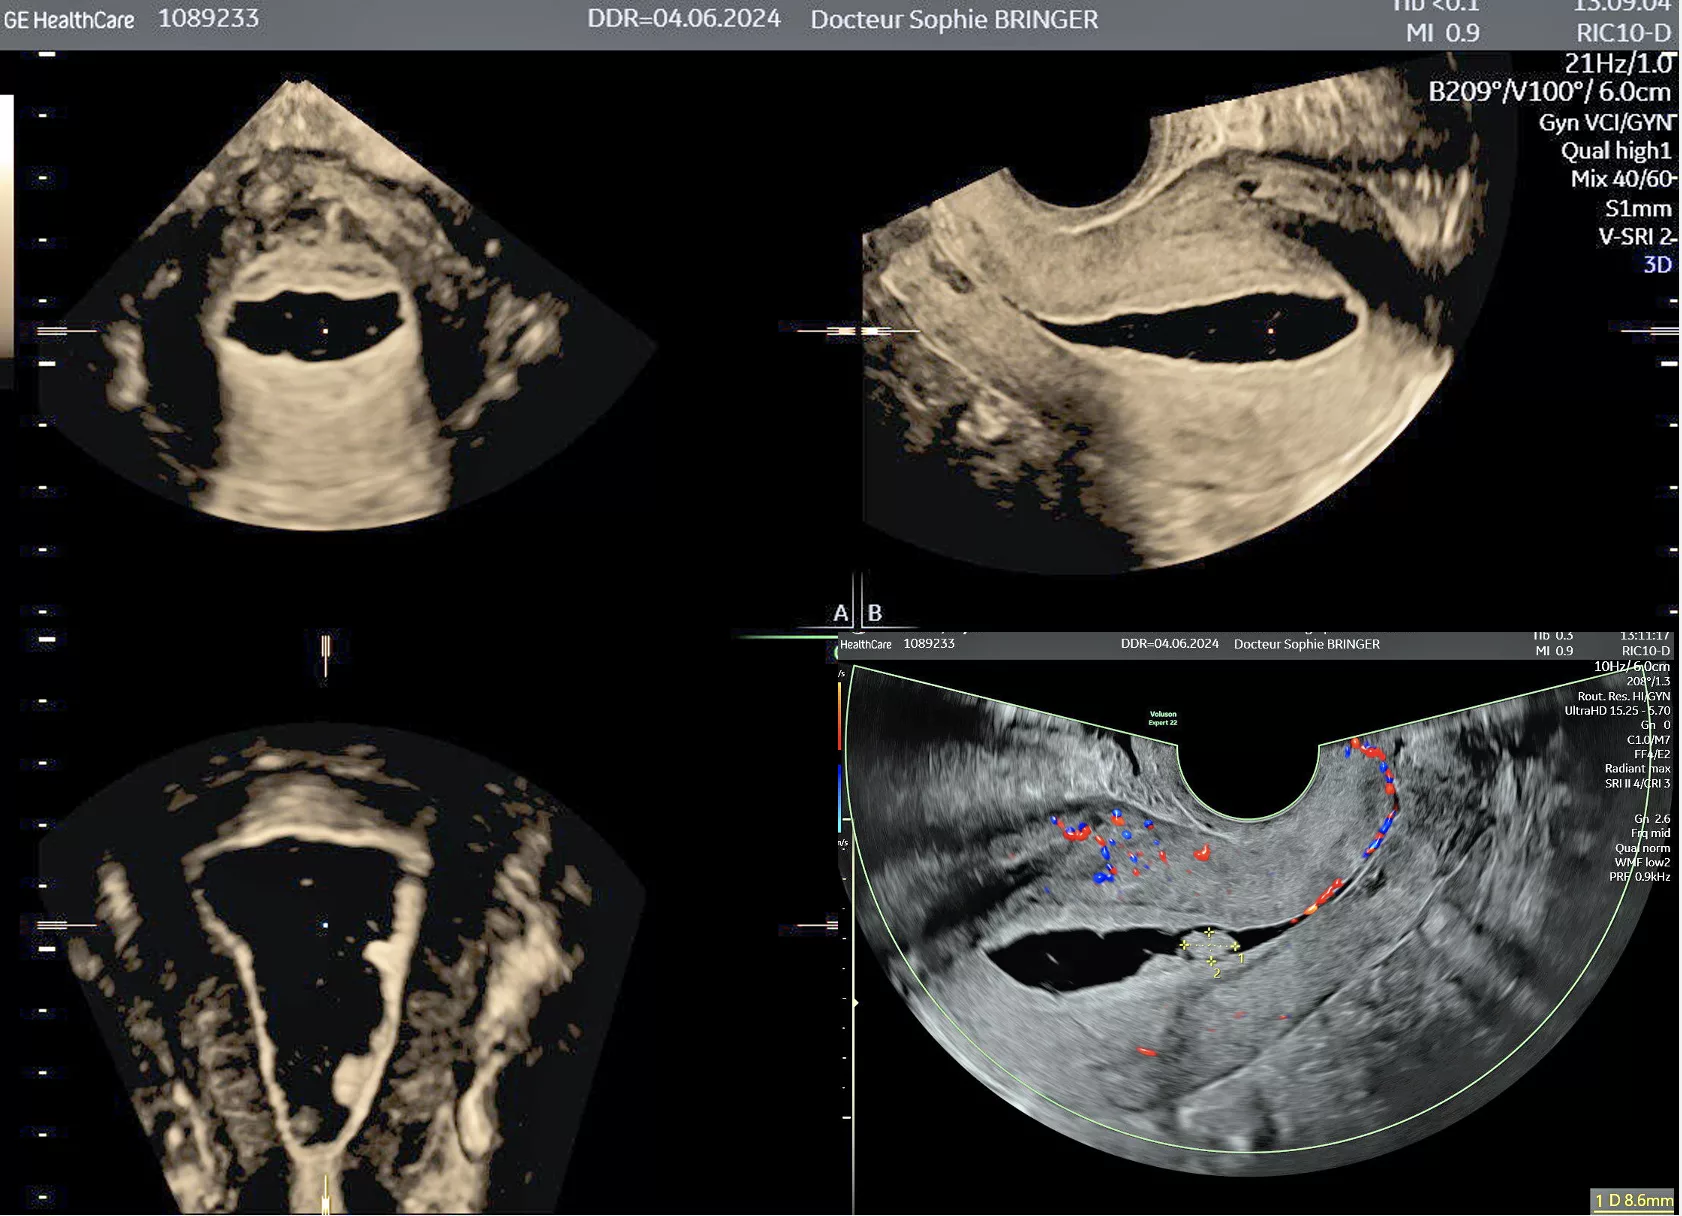

L'Hystérosonographie

Il s’agit d’une échographie pelvienne réalisée par voie endo-vaginale utilisant l’injection de sérum physiologique comme produit de contraste dans la cavité utérine.

Indication de l’examen :

- Bilan d’infertilité

- Diagnostic d’une malformation utérine

- Bilant devant des saignements anormaux

- Bilan de surveillance de l’endomètre

- Le spéculum est retiré et la sonde d’échographie est introduite dans le vagin. On pratique ensuite l’échographie tout en injectant quelques millilitres de sérum physiologique dans la cavité utérine.